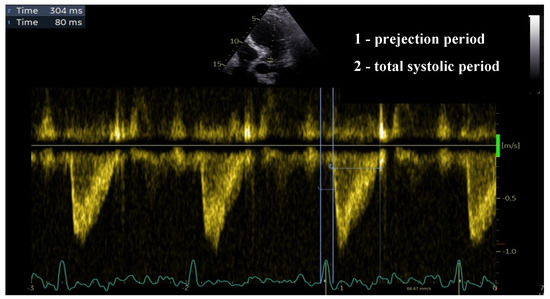

Isovolumetric Contraction as a Marker of Ventricular Performance in Patients with Afterload Mismatch

Introduction: The evaluation of myocardial contractility is essential in cardiology practice. The gold standard for this evaluation is the end-systolic elastance, but it the method involved is complex. Echocardiographic measurement of the ejection fraction (EF) is the most commonly used parameter in clinical [...] Read more.

Introduction: The evaluation of myocardial contractility is essential in cardiology practice. The gold standard for this evaluation is the end-systolic elastance, but it the method involved is complex. Echocardiographic measurement of the ejection fraction (EF) is the most commonly used parameter in clinical practice, but it has significant limitations, especially in patients with afterload mismatch. In this study, the area under the curve (AUC) of the isovolumetric contraction was measured to evaluate the myocardial contractility in patients with pulmonary arterial hypertension and severe aortic stenosis. Methods: 110 patients with severe aortic stenosis and pulmonary arterial hypertension were included in this study. The AUC of the isovolumetric contraction was measured using pressure curves of the right ventricle–pulmonary artery and left ventricle–aorta ascendens. This AUC was then correlated with the echocardiographically measured EF, stroke volume (SV), and total ventricular work. Results: The AUC of the isovolumetric contraction showed a statistically significant correlation with the EF of the corresponding ventricle (p < 0.0001). Both the AUC of the isovolumetric contraction and the EF showed a statistically significant correlation with the total work of the ventricle (AUC: R2 0.49, p < 0.001; EF: R2 0.51, p < 0.001). However, the SV only showed a statistically significant correlation with the EF. A statistically significant one-sample t-test could be found for the EF (decreased, p < 0.001) and for the AUC of the isovolumetric contraction (increased, p < 0.001), but not for the total work of the ventricle. Conclusion: The AUC space of the isovolumetric contraction is a useful marker of ventricular performance in patients with afterload mismatch, showing a statistically significant correlation with the EF and the total ventricular work. This method may have potential for use in clinical practice, especially in challenging cardiological cases. However, further studies are needed to evaluate its usefulness in healthy individuals and in other clinical scenarios. Full article